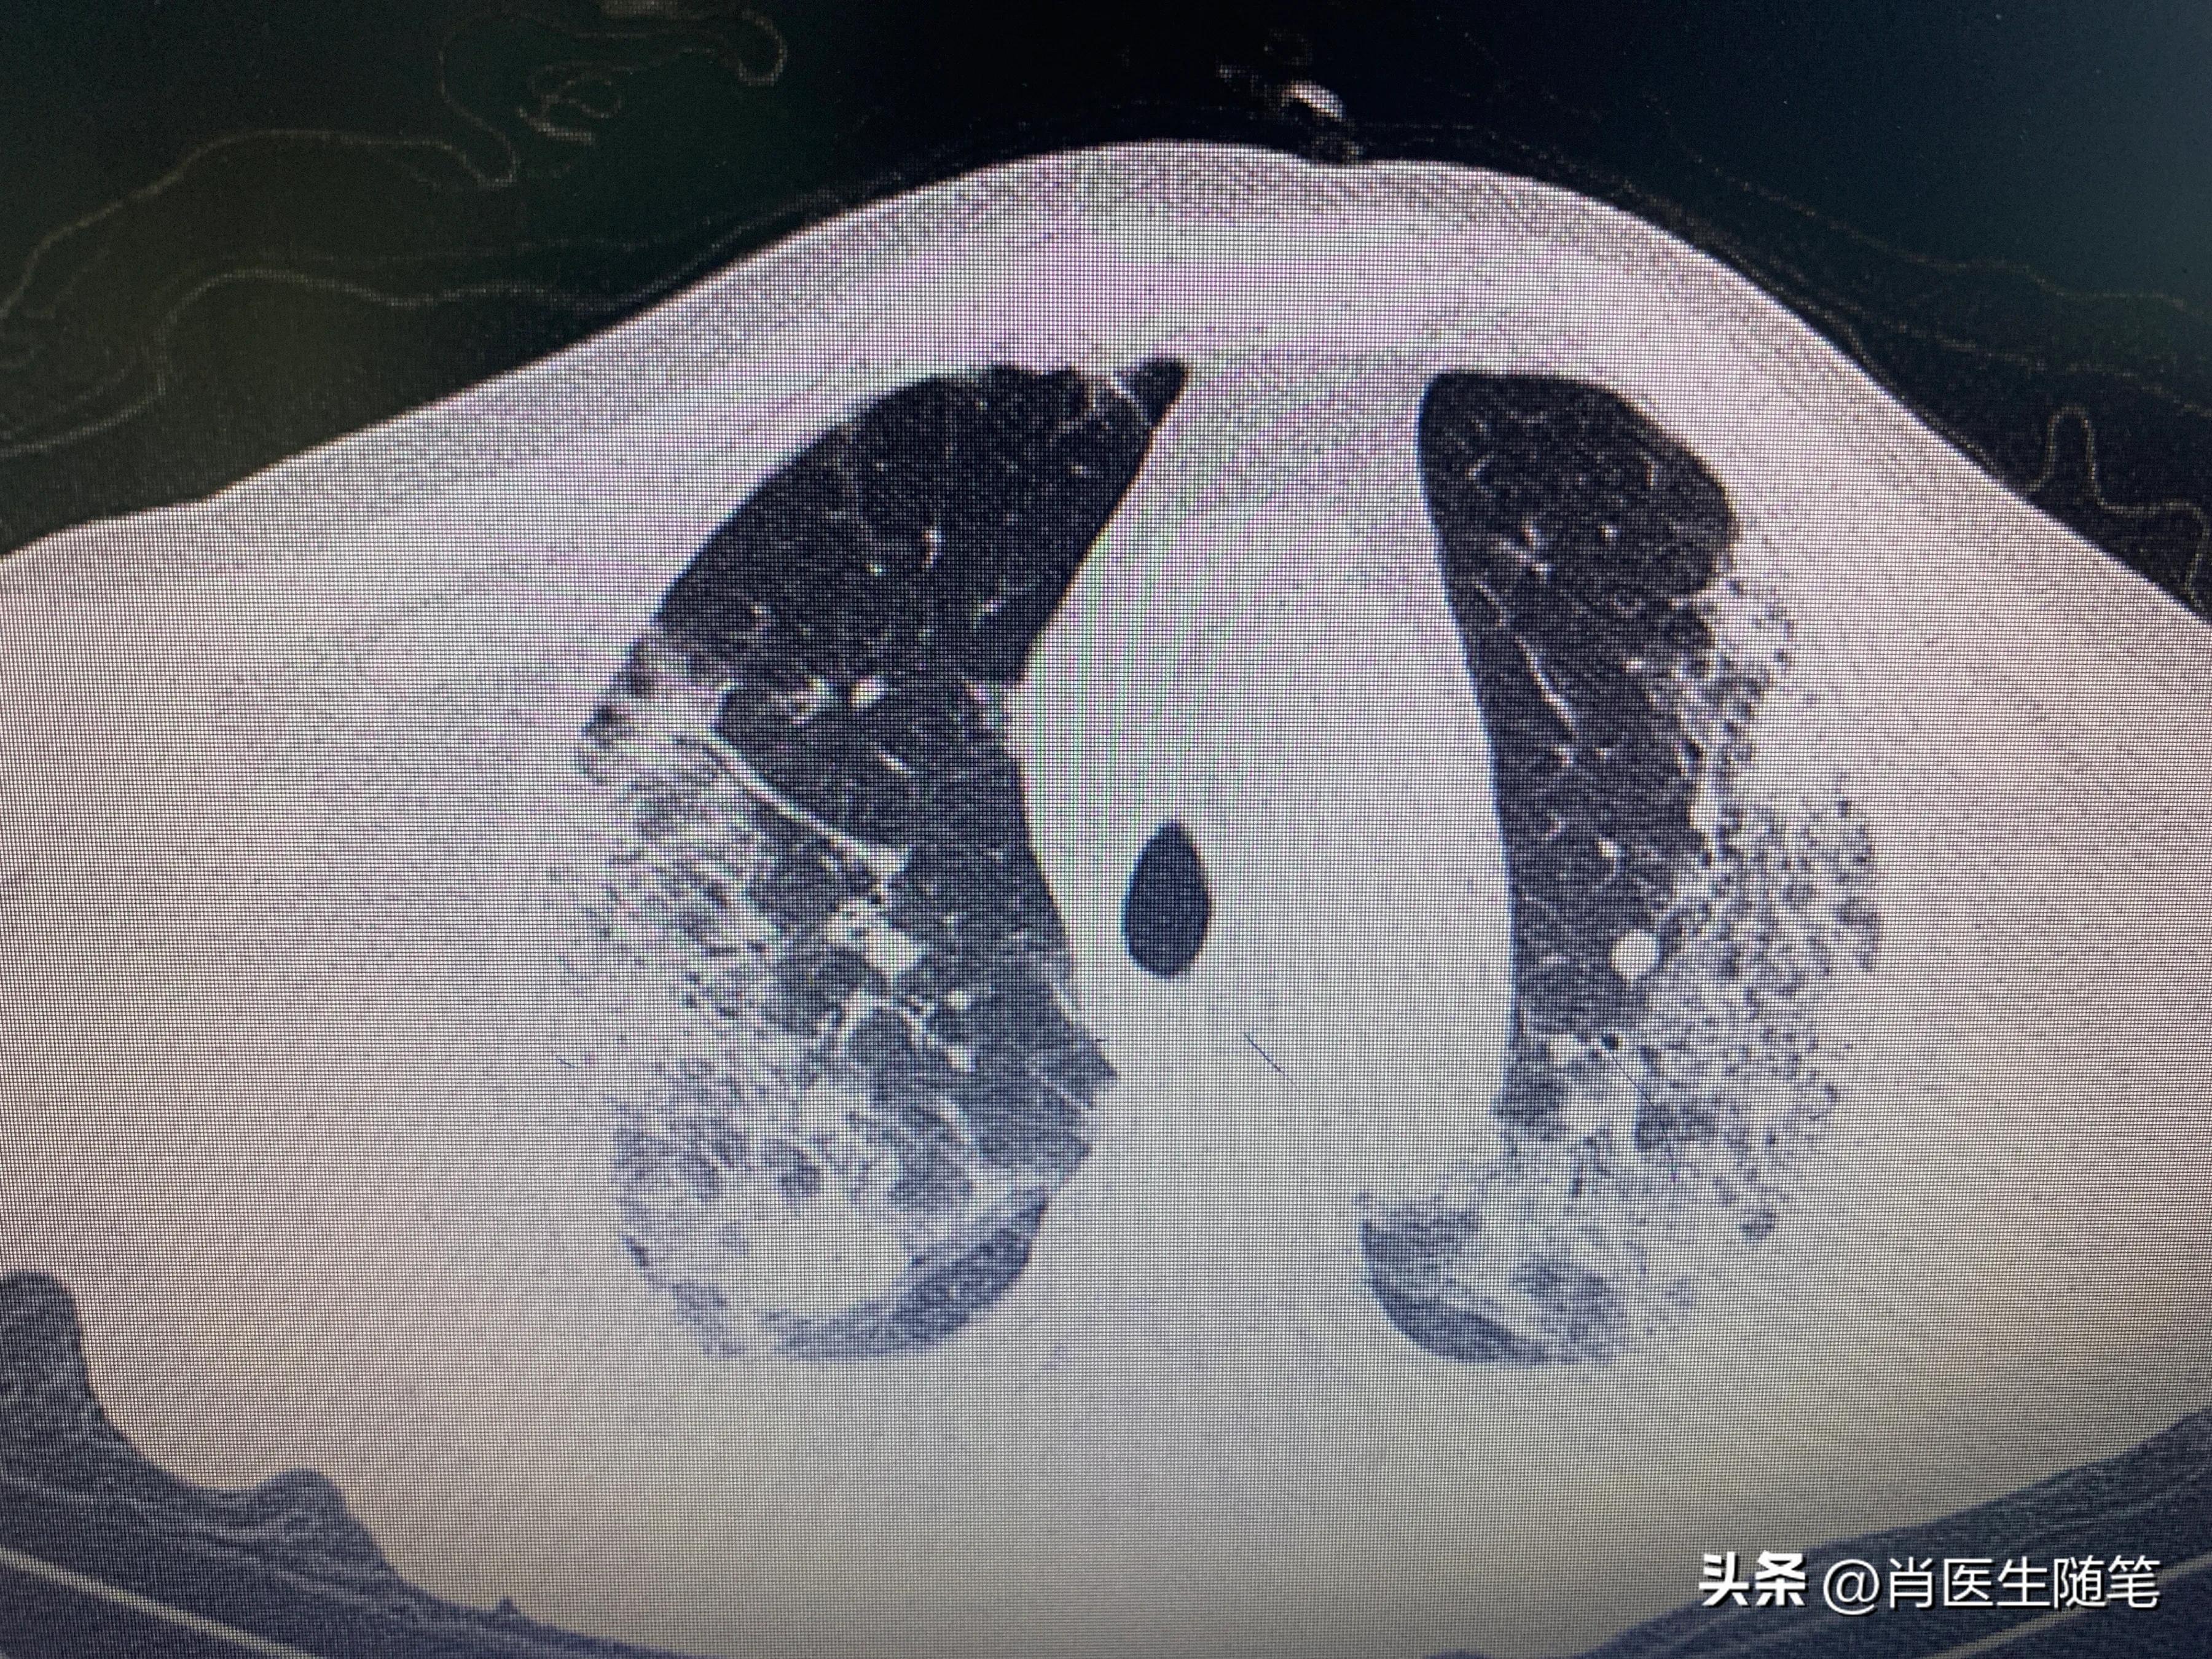

入院后2023-01-13胸部CT提示双肺炎症,纵膈多发淋巴结显示,部分钙化,双侧胸腔积液,心包积液。血提示炎症指标升高,白蛋白略低,33g/l。血氧饱和度吸氧下95%。

治疗后(2023-01-25)复查胸部CT,炎症较前吸收,下图是同样切面对比图。左边是13号的,右边是25号的。